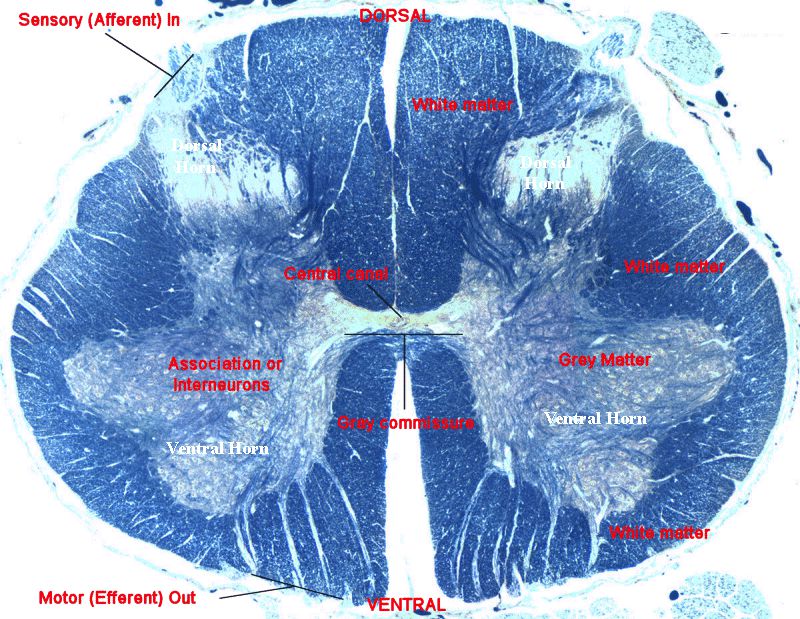

Đại thể cắt ngang tuỷ sống

Quan sát một lát cắt ngang, ta thấy:

- Rãnh giữa trước (có động mạch đốt sống trước) và rãnh giữa sau

- Chất trắng (White matter) nằm ngoài

- Chất xám (Gray matter) nằm trong. Có thể chia thành 4 phần: sừng trước (neuron vận động), sừng sau (cảm giác), vùng trung gian (neuron phối hợp), và sừng bên (phần của vùng trung gian, ở đoạn ngực và thắt lưng nơi có các neuron giao cảm)

- Ống trung tâm (Central canal): xuất phát từ não thất bốn chạy suốt trung tâm hành tuỷ và tuỷ sống; được lót bởi các tế bào nội ống tuỷ (ependymal cells) và chứa dịch não tuỷ

- Rễ bụng (Ventral root): Vận động, đi ra từ sừng trước. Về lâm sàng lưu ý 10 cơ thường sử dụng để định mức khoanh tuỷ, ví dụ cơ tam đầu: C7, cơ tứ đầu đùi: L3

- Rễ lưng (Dorsal root): cảm giác: đi vào sừng sau. Về lâm sàng cần ghi nhớ các khoanh cảm giác thường khám để định mức khoanh tuỷ. Ví dụ: Ngón tay giữa: C7; ngón út: C8; Vú: T4; Rốn: T10; Gối: L3; Mắt cá trong: L4; ngón chân út: S1; hậu môn: S3/Co

- Rễ lưng và rễ bụng nhập vào nhau để hình thành một dây thần kinh sống, chi phối cho các vùng cơ thể từ cổ trở xuống.

Một số thuật ngữ giải phẫu:

- gray commissure – Mép/chỗ nối chất xám (mảnh ngang chất xám ở trung tâm, bao quanh ống trung tâm và nối chất xám hai bên).

- central canal – Ống trung tâm (xuất phát từ não thất bốn chạy suốt trung tâm hành tuỷ và tuỷ sống; được lót bởi các tế bào nội ống tuỷ (ependymal cells) và chứa dịch não tuỷ.

- anterior white commissure = ventral white commissure – mép chất trắng trước/bụng.

- posterior white commissure = dorsal white commissure – Mép chấm trắng sau/lưng.

- anterior gray horn = ventral gray horn – Sừng (chất xám) trước/bụng : chứa các thân tế bào vận động (truyền xuống) và các neuron trung gian, từ đó các trụ trục vận động đi ra tuỷ sống.

- posterior gray horn = dorsal gray horn – Sừng chất xám sau/lưng: chứa các thân tế bào của các neuron trung gian nhận thông tin cảm giác (đi lên).

- lateral gray horn – sừng chất xám bên: chỉ thấy ở các khoanh ngực, thắt lưng và cùng, chứa các thân tế bào thần kinh vận dộng tự chủ/tạng (và các neuron trung gian) từ đó các trụ trục vận động tạng đi ra tạo nên các rễ trước của thần kinh tuỷ sống; đây là trung tâm kiểm soát chính của hệ thần kinh tự động.